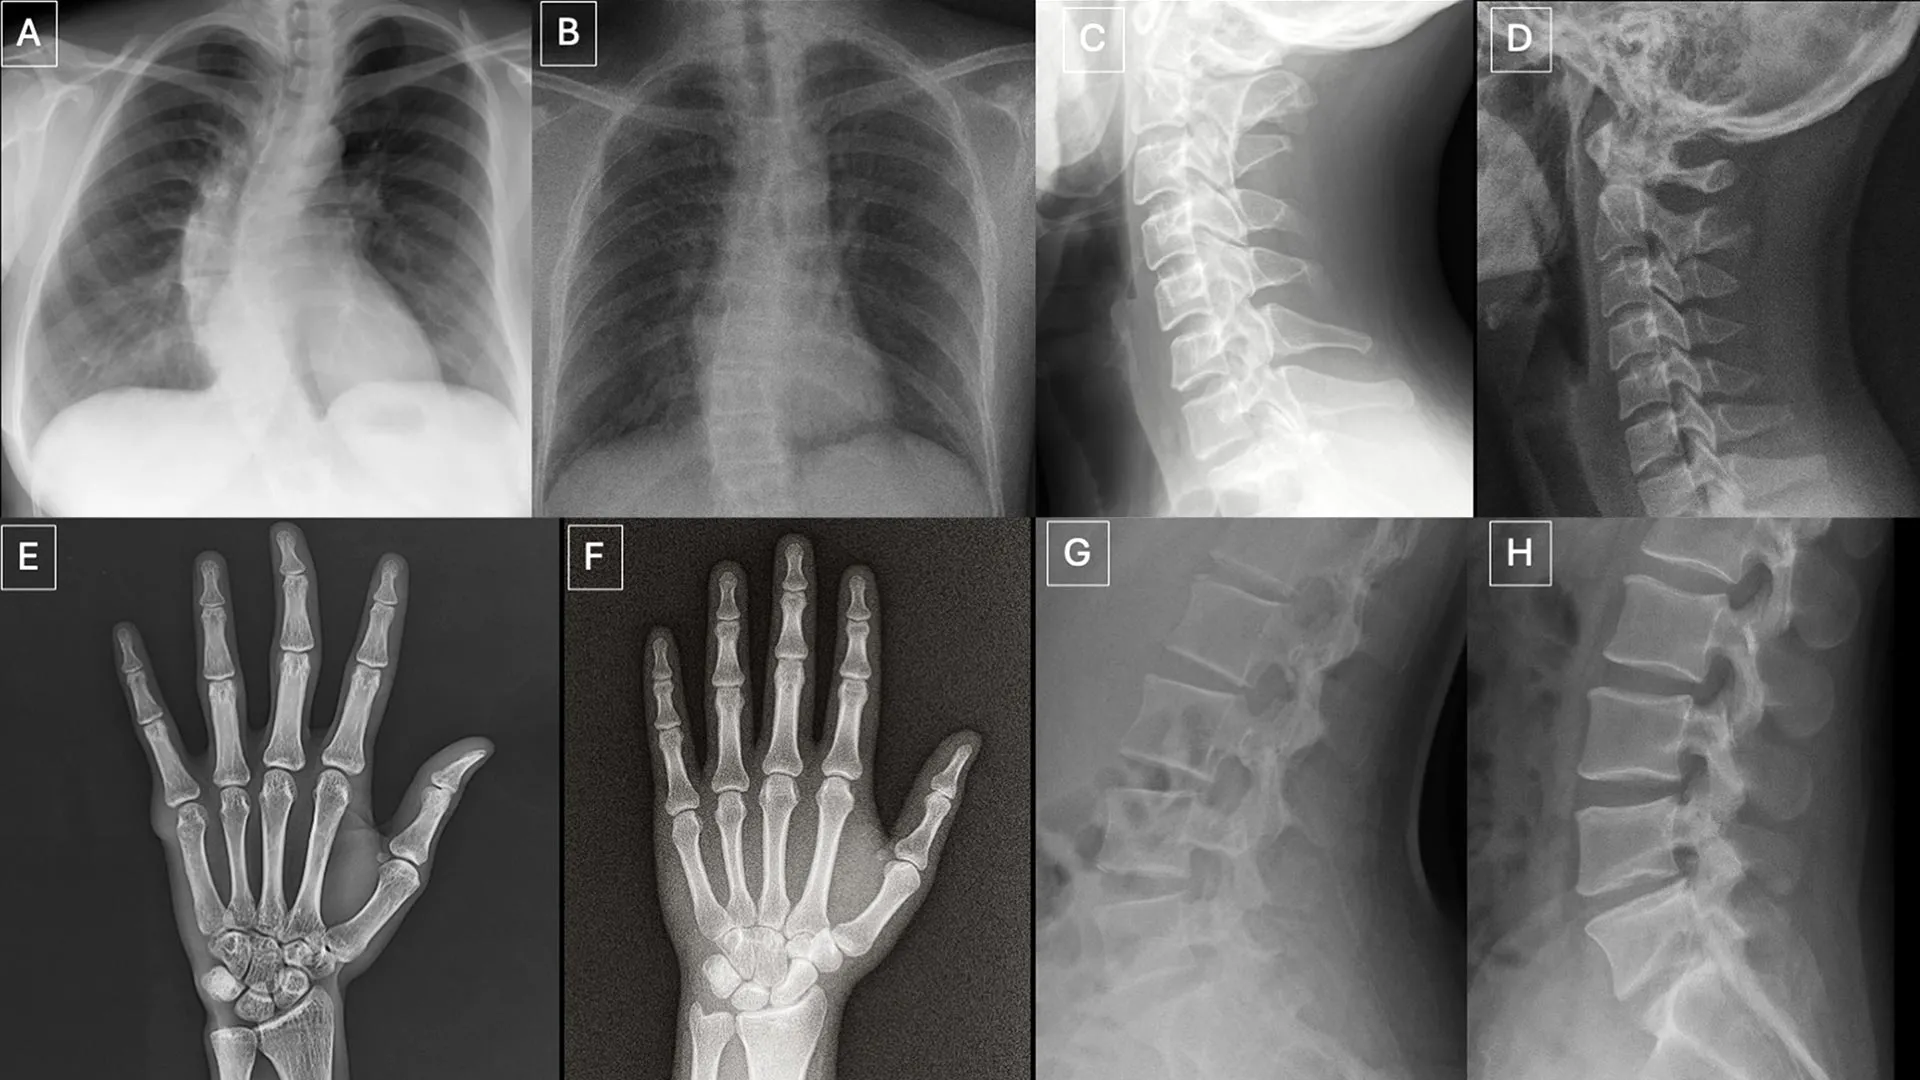

Os pesquisadores descobriram vários padrões que podem aparecer nas imagens compostas.

“Imagens médicas deepfake muitas vezes parecem perfeitas demais”, disse o Dr. Todjman. “Os ossos são muito lisos, a coluna vertebral é anormalmente reta, os pulmões são muito simétricos, o padrão dos vasos sanguíneos é muito uniforme e as fraturas parecem incomumente limpas e consistentes, muitas vezes limitadas a um lado do osso”.